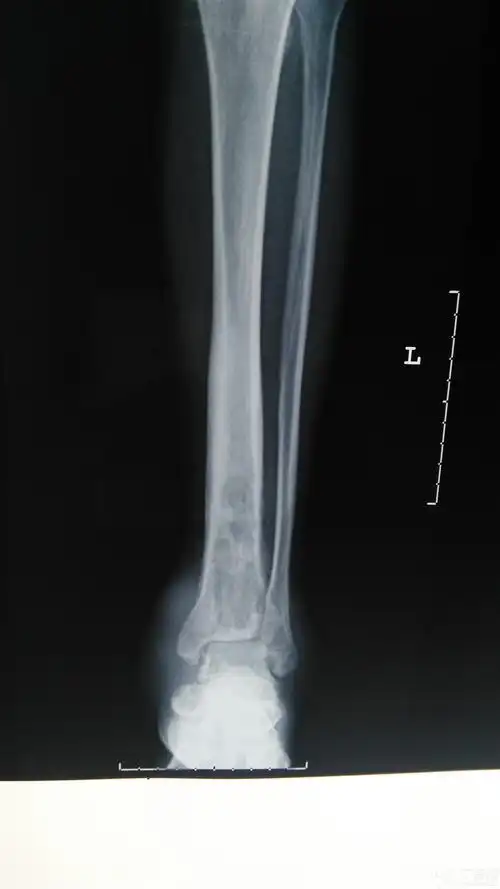

骨化脓性骨髓炎的影像学诊断

骨髓炎的影像学表现